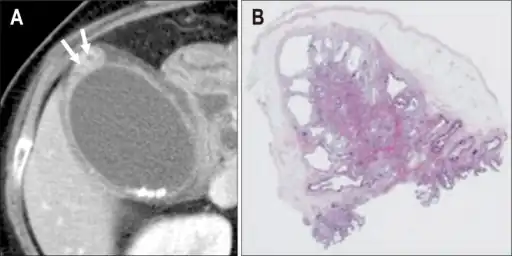

Micrograph showing Rokitansky–Aschoff sinus. H&E stain.

Adenomyomatosis is a benign condition characterized by hyperplastic changes of unknown cause involving the wall of the gallbladder.[1] Adenomyomatosis is caused by an overgrowth of the mucosa, thickening of the muscular wall, and formation of intramural diverticula or sinus tracts termed Rokitansky–Aschoff sinuses, also called entrapped epithelial crypts.

Rokitansky–Aschoff sinuses are pseudodiverticula or pockets in the wall of the gallbladder. They may be microscopic or macroscopic. Histologically, they are outpouchings of gallbladder mucosa into the gallbladder muscle layer and subserosal tissue as a result of hyperplasia and herniation of epithelial cells through the fibromuscular layer of the gallbladder wall.[3]

Magnetic resonance imaging also plays an important role in the diagnosis of Rokitansky–Aschoff sinuses.[10] In fat-suppression MRI, RAS present with small, rounded, high signal intensity foci, called “pearl necklace sign”.[9]